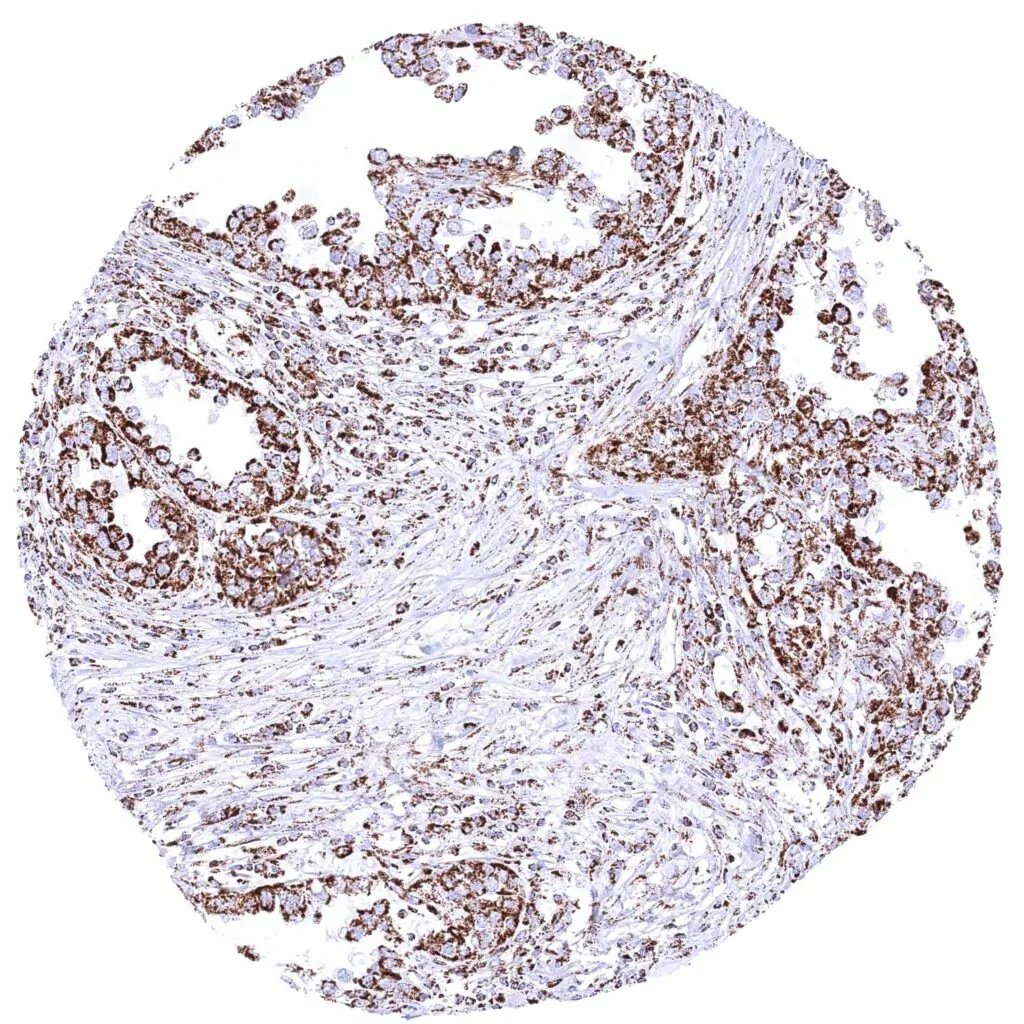

Soft tissue – Leiomyosarcoma with weak ATP5J staining of tumor cells.